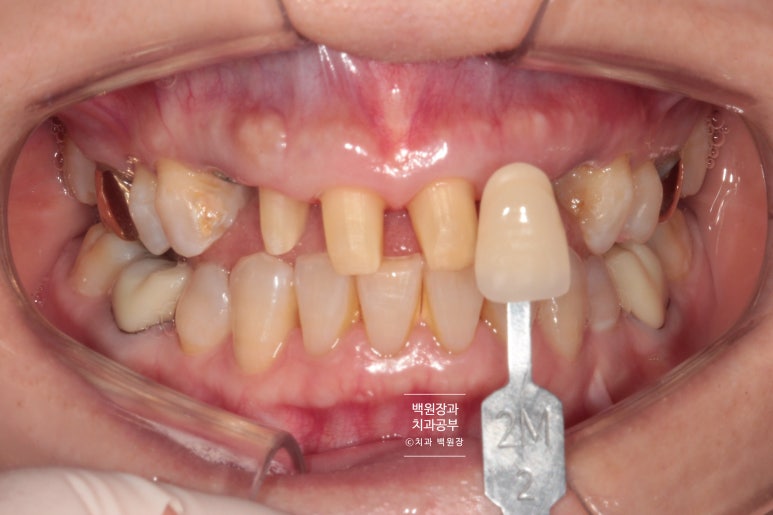

shade guide를 이용하여 제작할 색상을 기록합니다.

Vita shade guide 기준으로

2L 1.5는 조금 밝고 2M 2가 비슷해보이는데요, 원하신다면 앞니 지르코니아 크라운 치료시 보다 더 밝은 색상으로도 제작이 가능합니다! 환자분의 경우 자연스러운 색상을 원하셔서 2M 2로 선택하였습니다!